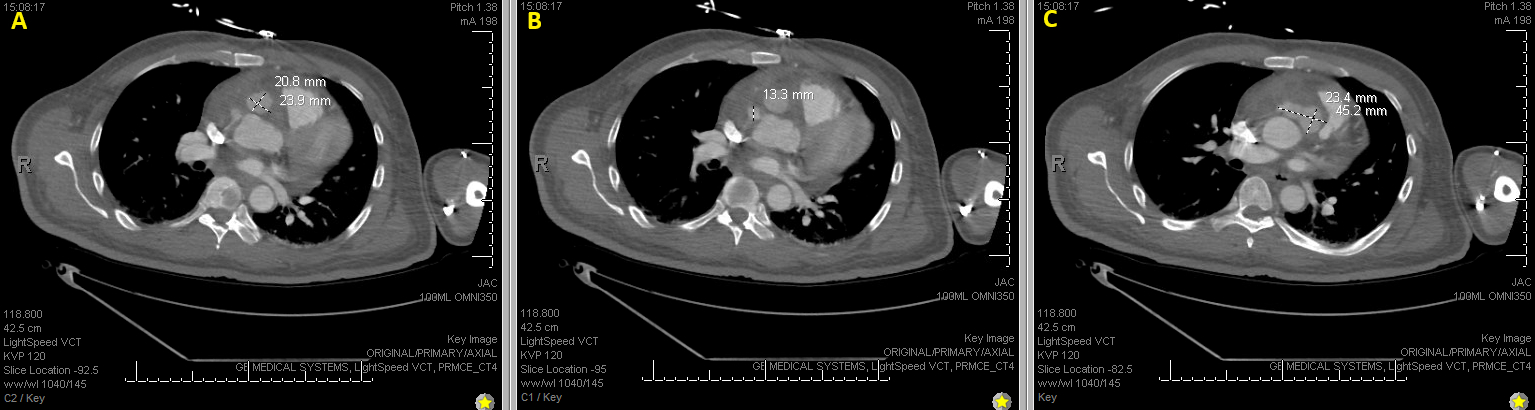

Abstract Body (Do not enter title and authors here): Description of Case: A 57 y.o. male with a hx of prior MSSA bactermia and RCA aneurysm presented for intermittent fevers. His exam showed a harsh systolic murmur at the pulmonic post. ESR and CRP were elevated at 78 mm/hr and 17.1 mg/dL, respectively. WBC of 32.1 x 10e3/uL and a HGB of 8.8 g/dL. Blood cultures were positive for MSSA. Imaging with a CTA Chest, TTE, TEE, and cardiac MRI showed a multilobular 5 x 2.5 x 5.3 cm PSA originating from the proximal ascending aorta.

It is worth noting is the compression of the pseudoaneurysm on the pulmonary artery. This is a very rare complication of ascending aortic pathology. In our patient, pulmonary artery compression was noted on his initial imaging and persistent throughout. However, right heart failure did not develop until his immediate post-operative course, and it’s possible that the necessary shifting of his pseudoaneurysm within his operation contributed to worsening compression on his pulmonary artery and subsequent mortality.